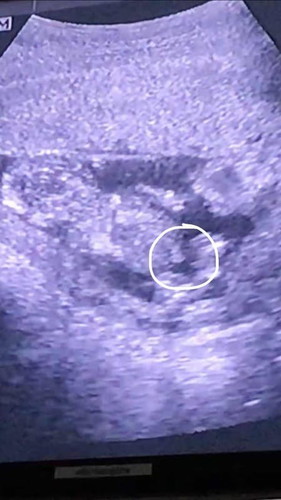

ขอสอบถามหน่อยค่ะแบบนี้สายสะดือหรือว่าจู๋ลูกค่ะตอนนี้13+1แล้วค่ะ #ขอบคุณล่วงหน้านะคะ #ลูกคนแรก #ท้องแรก

เหมือนสะดือนะคะ แต่ก็ไม่แน่ใจ